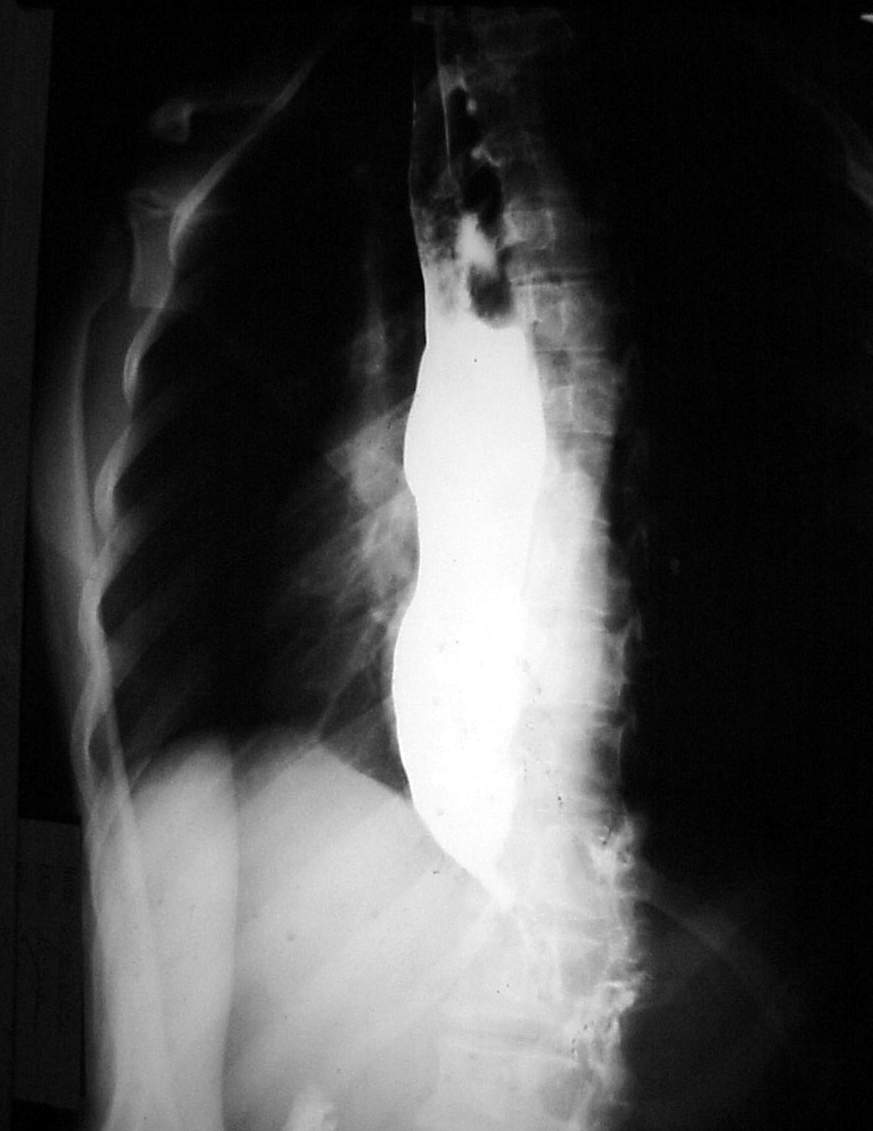

Pharynx and Esophagus Clinical Photos for Static Stations